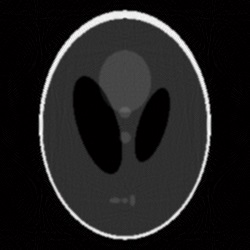

Given the problems we have pointed out regarding the first randomized algorithm, we have focused on the results obtained by the second randomized algorithm. For the parameters that we have fixed above, the results obtained by running the second randomized algorithm with 125000 iterations are given in Fig. 4 and Fig. 5 (Fig. 4 (a) is Fig. 2, and Fig. 5 (a) is Fig. 3). In both cases, the correction is significant, and the result of correction is very close in terms of reconstruction quality to the result obtained by running each of the two analytical algorithms alone with full view of 360 projection angles. That is, the result shown in Fig. 4 (b) is comparable to the result shown in Fig. 6, and the result shown in Fig. 5 (b) is comparable to the result shown in Fig. 7, which means a reduction in the number of views of (in Figs. 6 and 7 the reconstruction is more homogeneous, but with more visible artifacts). From the experiments we have conducted, we have remarked that the number of views can be reduced up to about and the results are still comparable to the results obtained by the analytical algorithms with full view, provided an appropriate number of iterations is chosen.